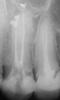

Вчера пошла по рекомендации к опытному доктору. Она посмотрела на шишку, потрогала, посмотрела снимки, и сказала что формируется свищевой ход,но гранулемы-то нет, и прошла прекрасно каналы сначала вживую,после болевой реакции под обезболиванием, сделали снимок каналы прйдены с выведением пасты. Поставили постоянную пломбу. теперь у меня вопрос. Доктор посоветовала в случае увеличения шишечки иссекать и чистить ее у хирурга. если сама не рассосется. Сегодня она еще на месте. Посоветуйте, иссекать ее или нет или есть какие-то местные средства. Гноя из каналов не было,жевать ни во ни до ни после лечения не больно. Антибиотики не назначила.post-15490-1291996784_thumb.jpgpost-15490-1291997099_thumb.jpgА это до перелечивания